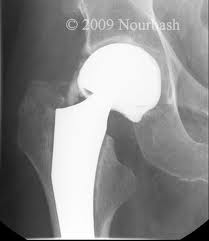

The implants used for the revision operation are broadly similiar to the ones used for first time sugery. They consist of a cup section inserted into the natural socket of the pelvis and a stem with a ball at its top aspect that is inserted into the femur bone. When the two are put together, a joint results much as is the case in nature where the ball at the top end of the thigh bone forms a joint with the hollow socket of the pelvis bone.

Acetabular Revision: There are two main techniques used for revising the acetabular component. In more complex cases however, a different approach may have to be taken. As is the case with primary or first time hip replacement surgery, revision of the socket can be carried out using components with cement or with components purpose designed to be used without cement.

Uncemented sockets: A technique that has gained increasing popularity in the last 7-10 years is the use of metal components without cement for revision of the acetabulum. These shells are very much like those used in primary surgery but have addtional holes provided so as to allow maximum flexibility to the surgeon is inserting supplemental screws. This is particularly useful where the bone is weak and the interference fit of the metal socket and bone, relatively poor.

Femoral Revision: With regards to the revising or redoing the femoral component, there are two broad trends. One is to rebuild the damage in the femur (thigh bone) with bone graft. This technique is called impaction grafting. The femoral component which is much like the one used in primary surgery, is then cemented into the grafted bone.